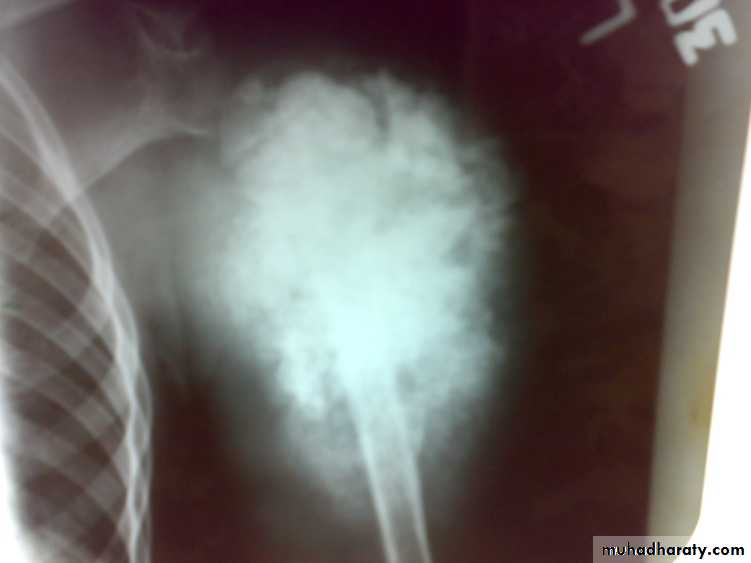

Osteosarcoma

primary malignant tumor arise from bone forming cells and produce malignant osteoid tissue. In addition to malignant osteoid tissue fibroblast or cartilage tissue may be predominate. It destroys the bone and form malignant osteoid and spread to surrounding tissue and metastasized to far organs.

: X-ray are very variable but it show combination of bone destruction and bone formation.

The metaphysis show osteolytic and osteoblastic areas, the cortex is usually perforated and soft tissue shadow may be seen.

There is new bone formation in form of Codman's triangle at periphery of when cortex penetration cause periostium elevation and vertical streaks of calcification in the adjacent soft tissues called sunray appearance.